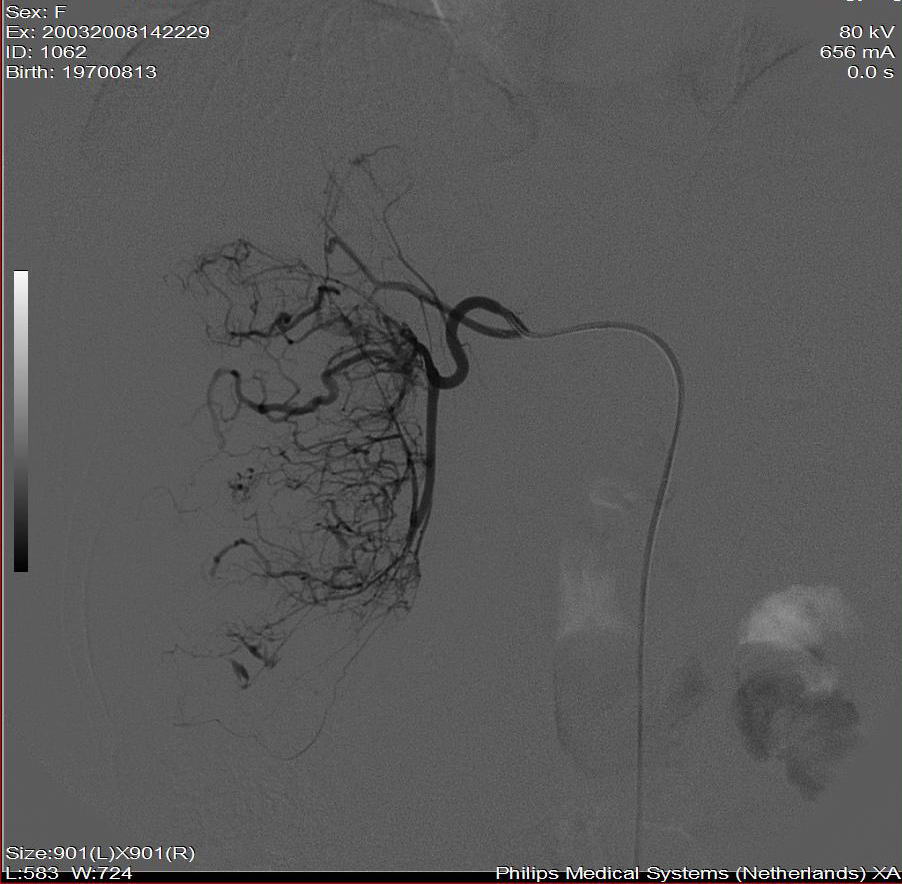

标题: DSA0138:F38Y,肝脏病变

第一次:

好牛的,右肝动脉发自肠系膜上动脉,不用微导管分次进行末梢栓塞,肿瘤染色完整。再次学习了。

漂亮!请问jiajie兄第一次打了多少ml栓塞剂?病人耐受情况如何?